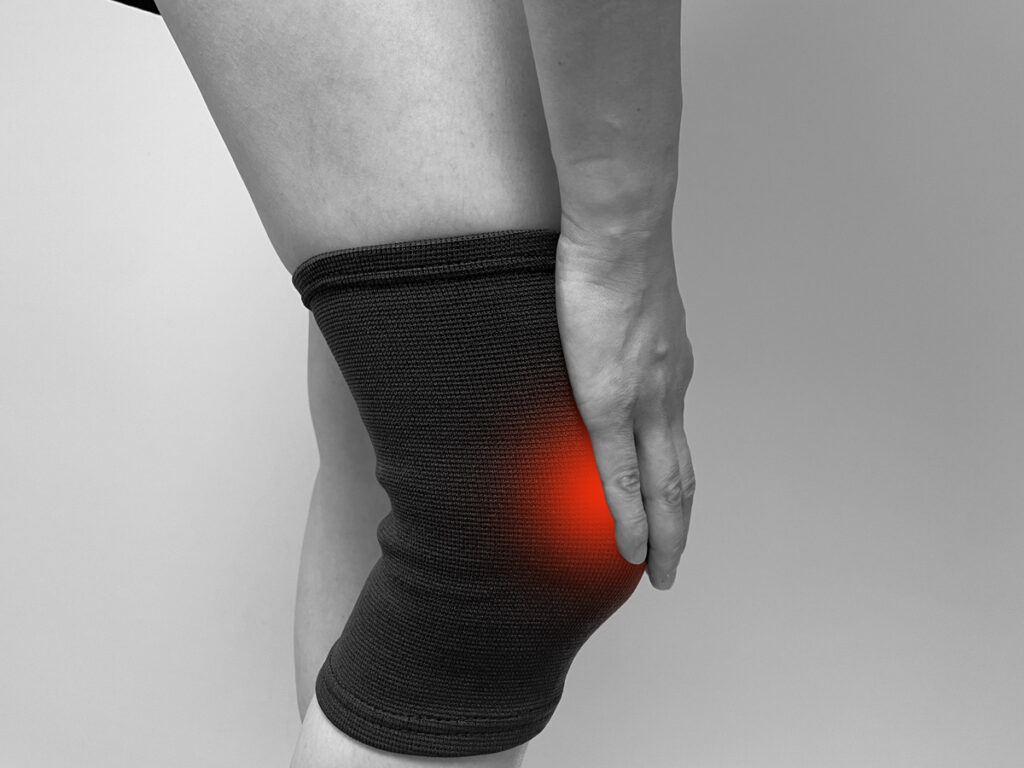

高齢になるにつれ、膝の痛みに悩まされる方は少なくありません。

動くたびに痛む膝に対し「サポーターは効果があるのかな?」と悩んでいる方もいるのではないでしょうか。

高齢者の膝の痛みは、適切なサポーターの使用によって、痛みをやわらげることが期待できます。

高齢になると関節の変形や筋力の低下により、膝関節に負担がかかりやすくなります。

サポーターには、筋肉の働きを補助し、関節の負担を軽減する効果が期待できるため、使用することで膝の痛みをやわらげられる場合があるのです。